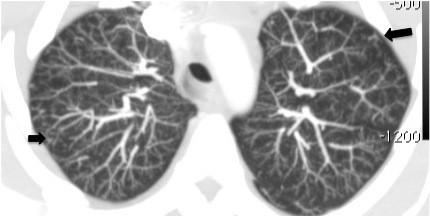

A 28-year-old Caucasian woman with a previous history of pelvic tumor resection two months previously, suggestive of metastatic adenocarcinoma, presented with intense shortness of breath. A computed tomography scan showed signs of acute cor pulmonale and diffuse nodular opacities associated with a tree-in-bud pattern disseminated through her lungs, suggestive of bronchiolitis. Our patient's condition worsened and she underwent a surgical biopsy. Pathologic analysis of the biopsied specimens revealed pulmonary tumor thrombotic microangiopathy. Our patient's tumor evolved from a gastric origin (Krukenberg tumor). She underwent progressive clinical deterioration and died less than 24 hours after the biopsy. None of the cases described previously in the literature had diffuse centrilobular nodular opacities associated with a tree-in-bud pattern disseminated through the lungs, as in our case.

Pulmonary tumor thrombotic microangiopathy should be considered in cancer patients with rapidly progressing dyspnea, chest computed tomography findings compatible with pulmonary hypertension and typical findings of inflammatory bronchiolitis.